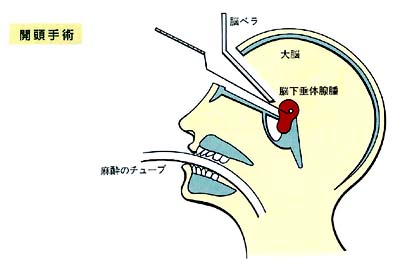

開頭手術

この手術の特徴

多くの場合は、右前頭側頭開頭術を行ないます。

まず、額の髪の生え際に沿って右前頭側頭部に皮膚切開を行ない、皮膚を翻転します。額の骨(前頭骨)を露出し、これに小開頭を加え、さらに脳を覆っている硬膜を切開します。

以上の操作で右の前頭葉と側頭葉と呼ばれる脳がみられ、この両者のすき間から手術用の顕微鏡を用いて下垂体部に到着し、腫瘍の摘出をします。

この場合、腫瘍の近傍には視神経や内頸動脈が直接みられます。腫瘍の摘出が終われば、硬膜を細かく縫合して、骨弁を元に戻して頭皮を縫合します。

この際、骨と硬膜の間にドレーンという管を留置し、血液の貯留を防ぎます。このドレーンは、手術後2〜3日以内に抜去します。

- 経鼻的手術に比べ術野が広く硬い腫瘍や頭蓋内に大きく広がった腫蕩にも用いることが出来ること、

- 頭蓋内に何らかの合併病変がみられる場合に、同時に処理することも可能であること、等が挙げられます。

一方、この手術法の欠点としては、先に経鼻的手術の長所として述べた面の裏返しとともに、下垂体内に限局する小さな腺腫は手術出来ないこと、手術後にまれにけいれん発作を来す可能性があること等です。